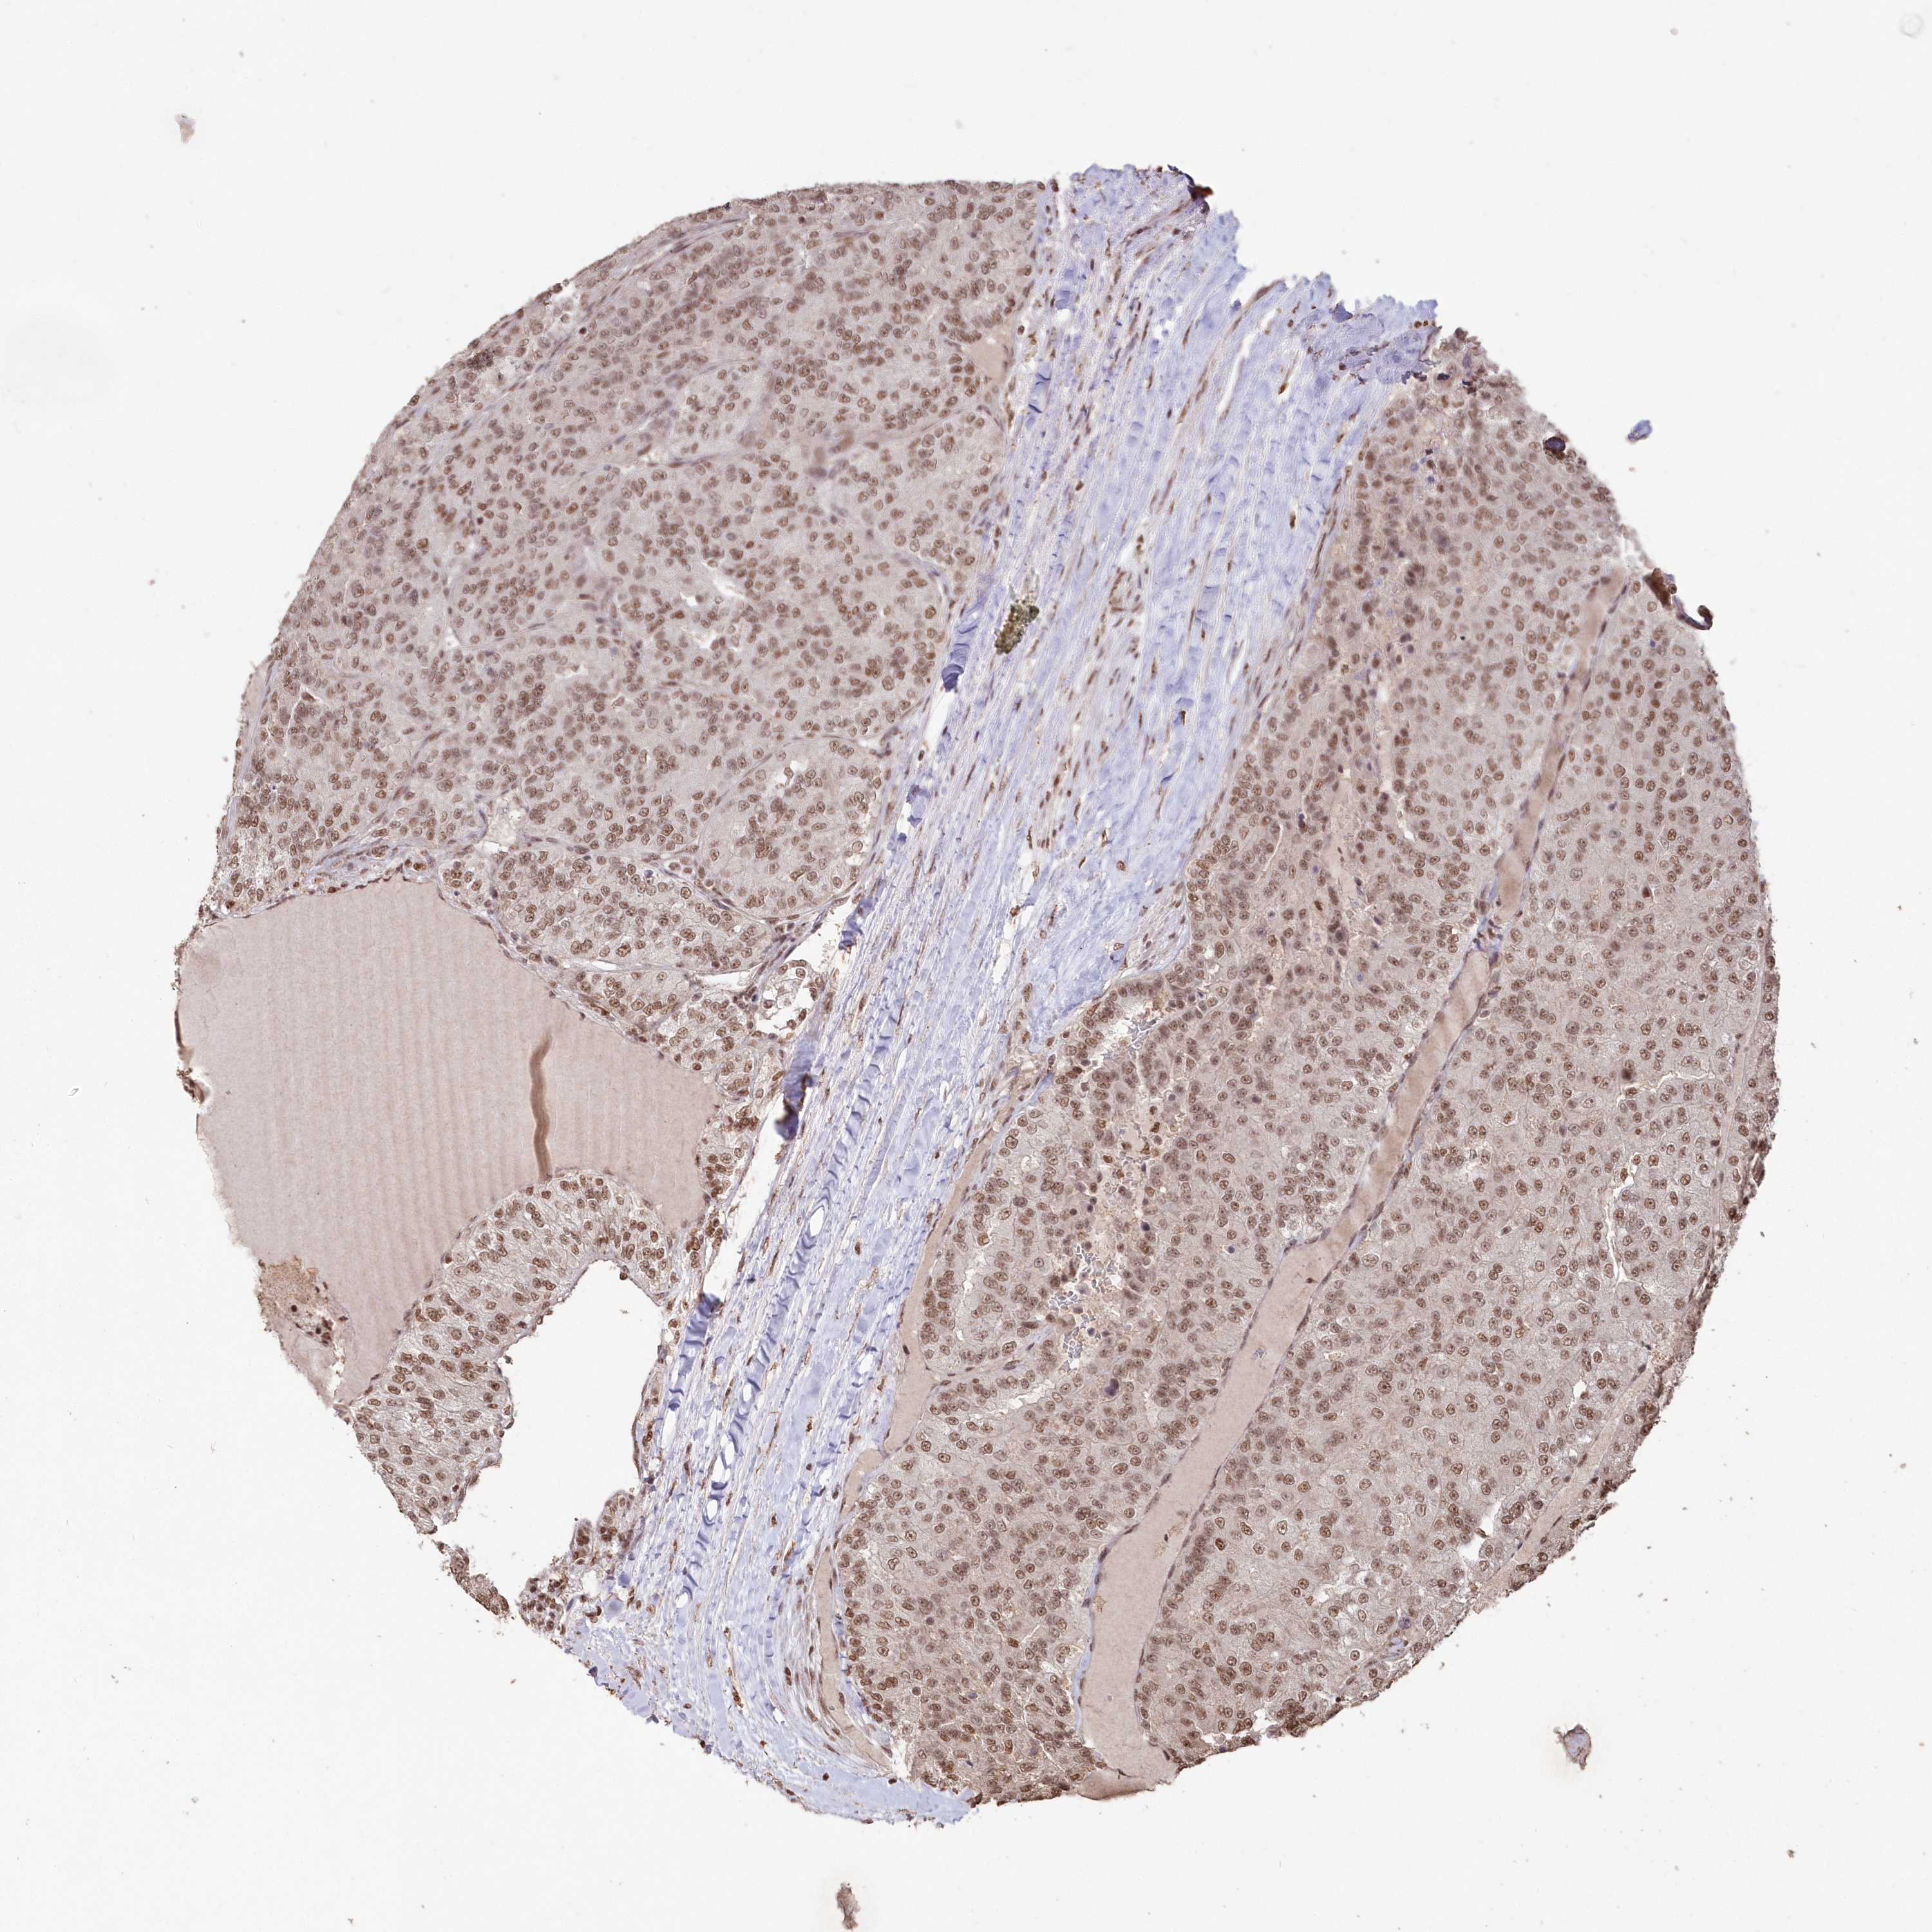

KIDNEY RENAL CLEAR CELL CARCINOMA (TCGA) - Interactive survival scatter ploti

The Survival Scatter plot shows the clinical status (i.e. dead or alive) for all individuals in the patient cohort, based on the same data that underlies the corresponding Kaplan-Meier plots. Patients that are alive at last time for follow-up are shown in blue and patients who have died during the study are shown in red.

The x-axis shows the expression levels (FPKM) of the investigated gene in the tumor tissue at the time of diagnosis. The y-axis shows the follow-up time after diagnosis (years). Both axes are complimented with kernel density curves demonstrating the data density over the axes. The top density plot shows the expression levels (FPKM) distribution among dead (red) and alive patients (blue). The right density plot shows the data density of the survived years of dead patients with high and low expression levels respectively, stratified using the cutoff indicated by the vertical dashed line through the Survival Scatter plot. This cutoff is automatically defined based on the FPKM cutoff that minimizes the p-score. The cutoff can be changed by dragging the vertical line or by entering a cutoff value in the square labeled "Current cut-off".

Under the Survival Scatter plot the p-score landscape (black curve; left axis) is shown together with dead median separation (red curve; right axis). Dead median separation is the difference in median mRNA expression between patients who have died with high and low expression, respectively. It is calculated as follows: median FPKM expression of dead patients with high expression - median FPKM expression of dead patients with low expression. This is intended to aid the user in visually exploring custom cutoffs and the associated p-scores and dead median separation.

Individual patient data is displayed and can be filtered by clicking on one or more of the category buttons on the top of the page. Categories describing expression level and patient information include: high, low, alive, dead, female, male and tumor stages. The scale of the x-axis can be toggled between linear and log-scale by clicking on the "x log" button. Mouse-over function shows TCGA ID, patient information and mRNA expression (FPKM) for each patient.

& Survival analysisi

Kaplan-Meier plots summarize results from analysis of correlation between mRNA expression level and patient survival. Patients were divided based on level of expression into one of the two groups "low" (under cut off) or "high" (over cut off). X-axis shows time for survival (years) and y-axis shows the probability of survival, where 1.0 corresponds to 100 percent.

PDS5A is potential prognostic, high expression is favorable in Kidney Renal Clear Cell Carcinoma (TCGA)

Best expression cut offi

Based on the FPKM value of each gene, patients were classified into two groups and association between prognosis (survival) and gene expression (FPKM) was examined. The best expression cut-off refers the FPKM value that yields maximal difference with regard to survival between the two groups at the lowest log-rank P-value. Best expression cut-off was selected based on survival analysis .

When clicking on this number, the vertical dashed line indicating cut-off, the interactive survival plot, and the Kaplan-Meier curve will be adjusted to show results based on the best expression cut-off.

: 16.72

TCGA RNA samplesi

RNA-seq data is reported as average FPKM (number Fragments Per Kilobase of exon per Million reads), generated by the The Cancer Genome Atlas (TCGA) .

Normal distribution across the dataset is visualized with box plots, shown as median and 25th and 75th percentiles. Points are displayed as outliers if they are above or below 1.5 times the interquartile range. FPKM values of the individual samples are presented next to the box plot.

Average pTPM 22.9

Number of samples 521